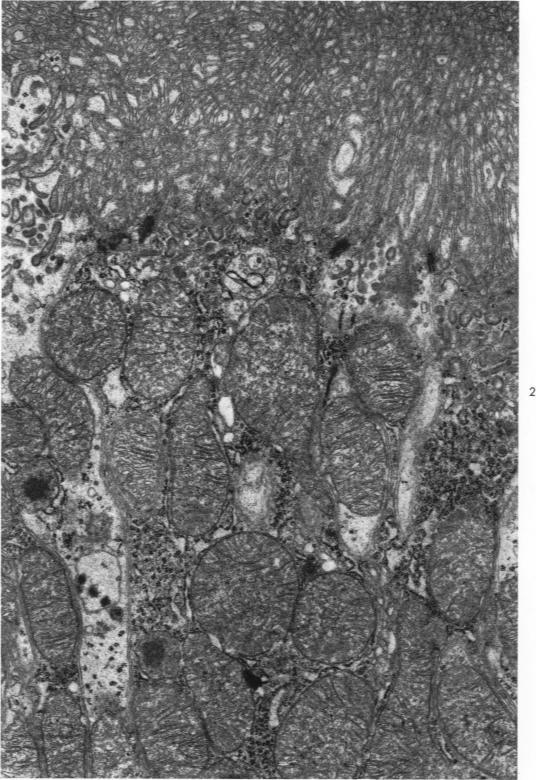

Structural and functional changes in rat kidney during CCl4 intoxication.

Am J Pathol. 1968 Nov;53(5):769-89.